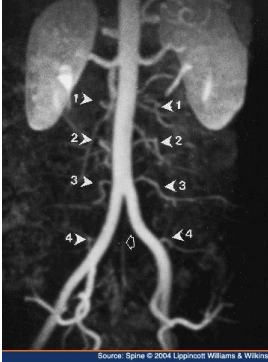

This is the arteriogram taken after Bernie referred his patient to a vascular surgeon. Truth be told: I wasn't surprised, but all his doctors were. Walking gave him pain in the calf and he didn't have a pulse in the ankle.

The pathophysiology of atherosclerosis also weakens the walls of arteries allowing for a bulging of the vessel known as an "aneurism." They are silent and deadly; it all begins with inflammation and atherosclerosis of the aorta, for example, or in the brain.

A narrowing of the artery by atherosclerosis of the aorta simply reduces blood flow to the various organs, notably the kidneys, the intestines and the spine; the brain and legs too.

Intermittent claudication causes pain in muscles whilst exercising, but quickly relieved by rest; it's a sure sign of an advanced stage of the pathophysiology of atherosclerosis.

This reduced blood flow to the legs produces a strange syndrome characterised by no symptoms whilst the sufferer is at rest, but pain in a muscle starved of oxygen as soon as it is forced to exercise.

Stopping the activity immediately alleviates the pain as the need for oxygen in the muscle is reduced.

Walking produces severe pain in the calf; cycling in the thigh muscle.

The sign your DC will look for to distinguish between claudication and sciatica is the presence of the pulse in the ankle and on the foot.